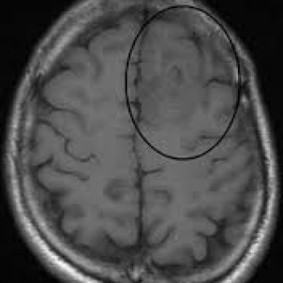

Glioblastoma Multiforme - University Of Missouri

Glioblastoma Multiforme. A . glioblastoma multiforme. is a malignant, primary brain tumor. It is the most common adult brain neoplasm, that has a rapid growth rate and complete surgical incision is impossible. ... View Document